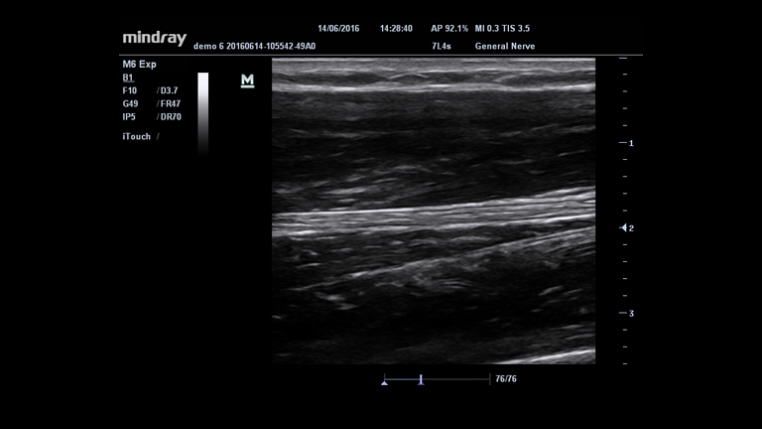

Gain improved image quality based on auto structure detection.

- Sharper & Continuous Edges

- Smooth Uniform Tissues

- Cleaner ŌĆśno echo areasŌĆÖ

Permits use of multiple scanned angles to form a single image, resulting in enhanced contrast resolution and improved visualization.